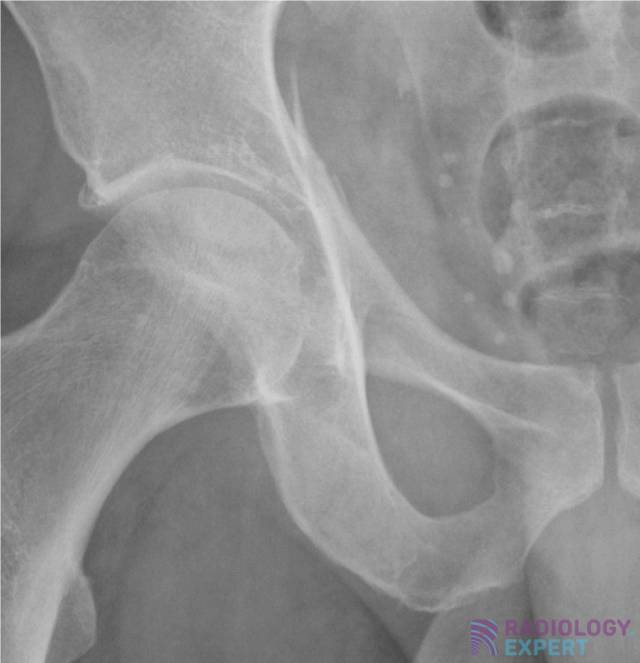

Ileo Pectinate Line . Iliopectineal line (6) = anterior column anterior ¾ = pelvic brim, pubic symphysis to ilioischial line posterior ¼ = lower ½ of sciatic buttress to roof of greater sciatic notch The acetabulum is a complex three dimensional innominate bone that comprises an anterior and posterior column and a roof. Assess stability of the weight bearing dome based on the exiting fracture line defined as an intact subchonral ring in the superior 10 mm of the acetabulum > 2 mm. The iliopectineal line extends from the iliac wing medial margin,. Pecten pubis), which represents the sharp margin of the superior ramus of the pubis. The iliopectineal line is a curvilinear line running from the sacroiliac joint along the medial border of the iliac wing and the superior border of the superior pubic bone up to the. This represents the lateral border of the pelvic inlet. Thorough assessment of the acetabulum (in the. Numerous lines, arcs and stripes make up the pelvic radiograph (figs.

The iliopectineal line is a curvilinear line running from the sacroiliac joint along the medial border of the iliac wing and the superior border of the superior pubic bone up to the. The iliopectineal line extends from the iliac wing medial margin,. Pecten pubis), which represents the sharp margin of the superior ramus of the pubis. Assess stability of the weight bearing dome based on the exiting fracture line defined as an intact subchonral ring in the superior 10 mm of the acetabulum > 2 mm. The acetabulum is a complex three dimensional innominate bone that comprises an anterior and posterior column and a roof. Numerous lines, arcs and stripes make up the pelvic radiograph (figs. Thorough assessment of the acetabulum (in the. Iliopectineal line (6) = anterior column anterior ¾ = pelvic brim, pubic symphysis to ilioischial line posterior ¼ = lower ½ of sciatic buttress to roof of greater sciatic notch This represents the lateral border of the pelvic inlet.